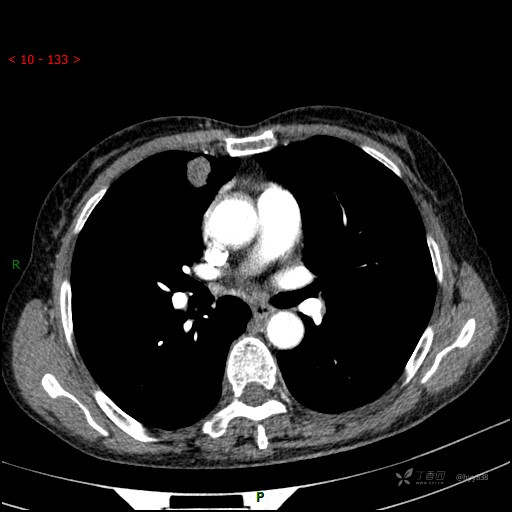

胸部CT平扫